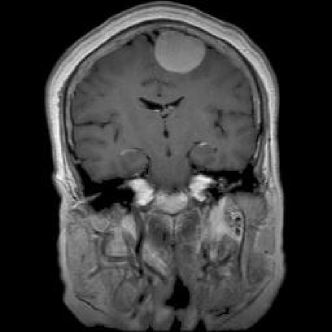

4.1.6 Brain MRI

Brain tumors pose significant health challenges, often impacting critical functions such as vision, balance, and cognition. Early detection is crucial for improving patient outcomes and quality of life. Through MRI scans, different conditions of the brain can be visually detected. The selected brain tumor dataset 666https://www.kaggle.com/datasets/sami009mr/brain-tumor-dataset contains 3,362 images across four categories: glioma, meningioma, pituitary tumors, and normal brains. Images illustrating the three aforementioned classes can be found in Fig. 7.

Refer to caption

(a) No tumor

(b) Glioma tumor

(c) Meningioma tumor

(d) Pituitary tumor

Figure 7: Brain MRI scans.